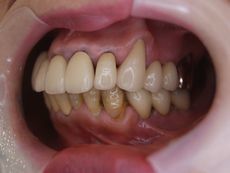

初診

DSC00325.JPG

DSC00322.JPG

DSC00326.JPG

インプラント治療後(以前のセラミックの冠はできるだけ残してます。)

義歯が無くなり、奥歯で噛めることは生活の質の向上につながると思います。

●● 様女性 60代

治療の期間・回数:5ヶ月、10回

治療の価格:20万円/1歯あたり